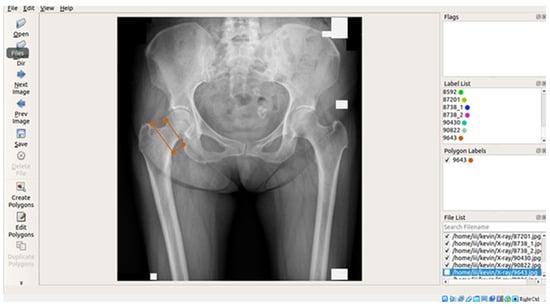

In this study, X-ray images of each of the four areas of the patient’s hip (femoral neck, greater trochanter, Ward’s triangle, and total hip) were separated and manually labeled using Labelme, an open-source tool that can be used for labeling [29]. The four parts of the hip were then framed as shown in Figure 2 below, and the labeled image data were batch converted into binary png files, which were used as inputs for the supervised learning training of U-Net, U-Net++, and image categorization in the image segmentation process.

Figure 2. Image labeling tool and interface.